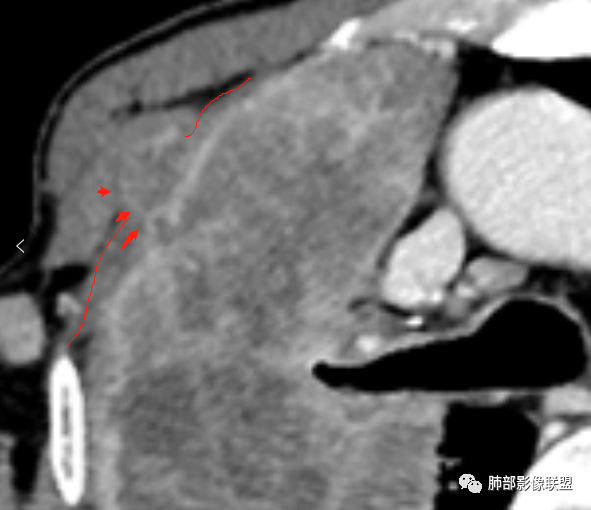

这就栽赃。都突到外面去了。

看看这个,骨头都侵袭了。

南边:一般这类侵袭,是中央地带毛刷状延伸到胸膜内。

我只是邓较瘦:南大这个我感觉局部似乎是栽赃呢 箭头那里是啥?

南边:栽赃是这样过去的,中间不会脂肪间隙清晰。

胸壁的组织,除非你怀疑胸壁转移结节。

转移淋巴结。

局部侵犯。有差异。

我只是邓较瘦:这个是侵犯出去不是淋巴结吧?

南边:不是,你看看强化与淋巴结不一致。

我只是邓较瘦:强化与肿瘤差不多。

南边:是。